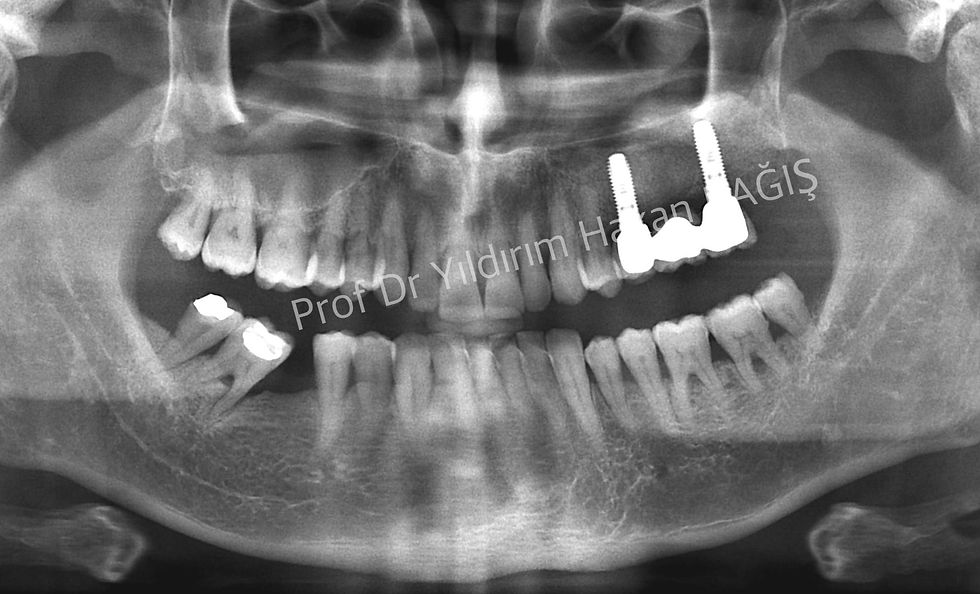

Üst çenede çiğneme alanlarında dişleriniz yok ve bu bölgede ağızda sabit kalan protezler istiyorsanız, tek çözümünüz implant uygulamalarıdır. Fakat, bazen üst çenedeki kemik istenilen kalınlıkta olmaya bilir. Bunun sebebi; adına, “maksiller sinus” denen kemiğin içindeki balon şeklindeki boşluktur. Sinüs Lifting veya sinüs yukarı alma bu balon şeklindeki boşluğun kemik benzeri bir madde ile doldurularak implant uygulamalarına hazır duruma getirilmesi işlemidir. Ne yazık ki, bu yöntem herkesin yapabileceği bir teknik değildir. Konusunda uzman kişilerin bile zorlanabileceği bir yöntemdir. Başarılı olmak ve üzerine diş yerleştirebilmek için günümüz şartlarında 6 ay beklenilmesi gerekir. Bazen operasyon başarısız olabilir ve maalesef hasta ve hekim yönünden olumsuzluklar olabilir. Mutlaka bu konular operasyon yapılmadan önce hastaya özenle anlatılmalıdır.